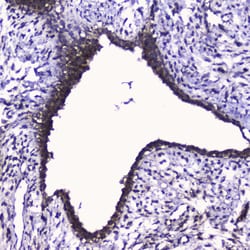

Invitrogen™ CDK6 Polyclonal Antibody

Reconstitute with 0.2 mL of distilled water to yield a concentration of 500 μg/mL. Positive Control - WB: human Hela whole cell, human Jurkat whole cell, human K562 whole cell, mouse RAW2647 whole cell. IHC: human intestinal cancer tissue, human mammary cancer tissue.

| Applications | ELISA, Immunohistochemistry (Paraffin), Western Blot |